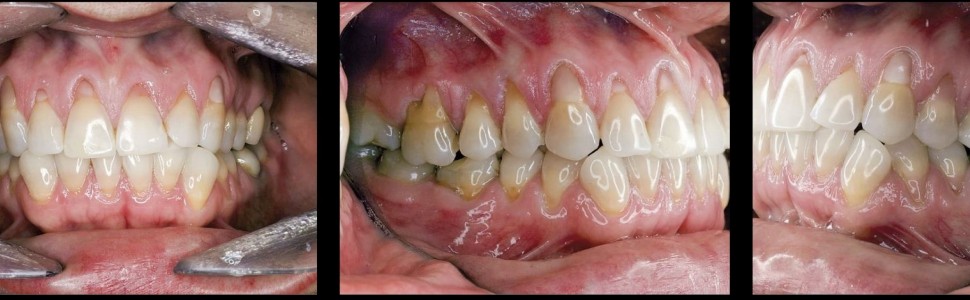

| Pacjentka w wieku 40 lat przed leczeniem. Mnogie (wysokie i szerokie) recesje dziąsła, ryc. 1 | Pacjentka w wieku 40 lat przed leczeniem. Mnogie (wysokie i szerokie) recesje dziąsła, ryc. 2 | |

| Pacjentka w wieku 40 lat przed leczeniem. Mnogie (wysokie i szerokie) recesje dziąsła, ryc. 3 | ||